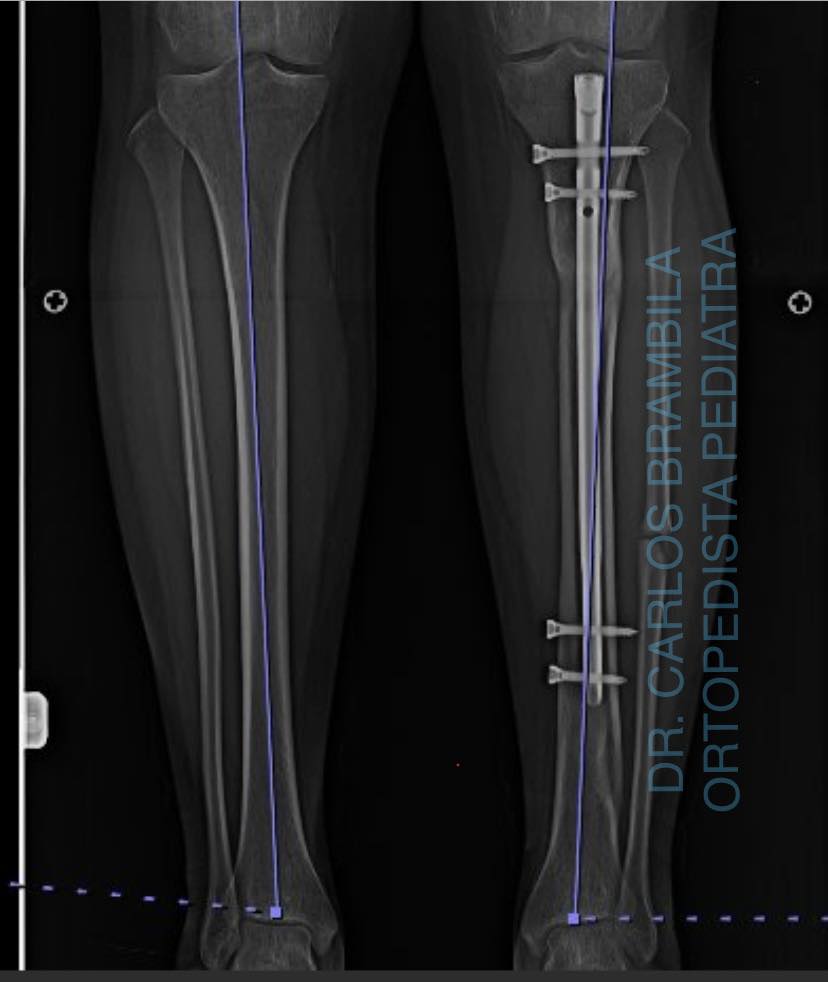

Hoy es un día especial y quiero aprovechar para compartir el caso de Emiliano, un joven de 17 años originario de Nayarit. Emiliano acudió conmigo por una deformidad en su pie, la cual había sido tratada quirúrgicamente en varias ocasiones sin éxito. Iniciamos un tratamiento con yesos, seguido de una cirugía para el balance neurológico del pie. Ahora, después de 5 meses, este es el resultado: Emiliano ya no necesita bastón para caminar y puede vivir libre y feliz.